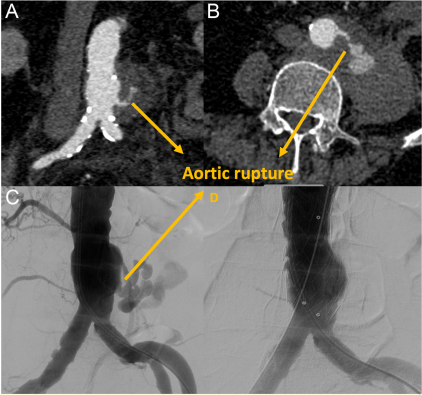

患者的实验室检查显示炎症标志物水平高,血培养阴性;C反应蛋白值、血红蛋白、白细胞计数分别为208 mg/L、11.2 g/dL、1.5000 cells/μL。通过血、尿和痰培养;结核病测试;以及胸部和腹部的CT成像排除其他部位感染。所有培养均为阴性,但测试是在患者口服抗生素治疗期间进行的。患者接受普通外科脓肿引流计划,静脉滴注哌拉西林-他唑巴坦和万古霉素抗生素治疗。入院后第3天血红蛋白降至7.8g/dL。CT血管造影显示腹主动脉非动脉瘤性破裂(图2A和B)。这一发现很可能是由于腰大肌脓肿侵蚀动脉壁的结果,而腰大肌脓肿在之前的CT扫描中没有扩张,并且血红蛋白值在过去一个月保持稳定。

该病例进行了临床会议上的讨论,心血管外科、心脏病学、介入放射学和普外科参与了讨论。为了防止危及生命的大出血,医生决定植入主动脉支架。植入直径28和长度82 mm的管状主动脉支架(Endurant II Medtronic, Santa Rosa, california, USA)(图2C和D)。术后患者在抗生素治疗下炎症症状消退,血红蛋白水平保持稳定。建议行主动脉手术及脓肿引流,但患者拒绝,在临床静脉抗生物治疗6周后出院。患者作为门诊随访,炎症标志物水平正常,无主诉。手术后,患者已经存活1年。

图2。(A-B)腰肌脓肿和腹主动脉破裂的冠状和轴位ct图像

(C)腹主动脉破裂的血管造影图

(D)主动脉破裂血管内支架植入治疗成功